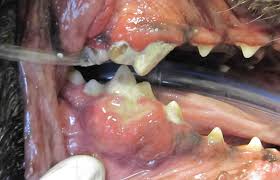

Oral Tumors In Dogs Cats Pets Pet Oral Cancer Veterinary Dentist Wisconsin Oshkosh Green Bay Greenfield Glendale Dr Kressin from www.mypetsdentist.com The photo on the left shows cutaneous lymphoma in the mouth of a dog. Gingiva cancer (also known as squamous cell carcinoma) is a progressive, rapid (weeks) local invasion of neoplastic epithelial cells within the oral cavity of dogs. Life expectancy, survival and prognosis. As most people like dogs more than humans, giving dogs the best care is a priority, including being on the lookout for signs of cancer. This cancer commonly develops in a dog's mouth. It can be malignant or benign. It looks like a skin. Abnormal cell growth usually appears as flat patches.

How To Detect And Treat Mouth Cancer In Dogs Angi Angie S List from media.angi.com The photo on the left shows cutaneous lymphoma in the mouth of a dog. Note the very red gums and the ulceration on the roof of the mouth. Specific signs will depend on where the tumor is located and may include a swollen paw, eye discharge or sores in the mouth. It looks like a skin. A canker sore looks like an ulcer, usually with a depression in the center. Here are some symptoms you can look for, options for treatment and the life expectancy for dogs with mouth cancer. Lumps and bumps underneath a dog's skin. Dog mouth cancer symptoms the mouth cancer in dogs will present several symptoms;

Melanoma, for instance, can show up as a dark spot in your dog's mouth or a swollen paw. Life expectancy, survival and prognosis. The average age of dogs impacted is about 11 years. Melanomas in dogs tend to affect the mouth and lips, and they can also be found on their nail beds, footpads and eyes. Melanoma is a type of cancer associated with pigment cells called melanocytes. A dog's mouth, similar to our own, is made up of several different cell types; Melanoma is the most common oral tumor in dogs. Canker sores can be found anywhere in the mouth from the cheek, inner lip, on and under the tongue, and even in the throat. Full staging including ct scanning is recommended to determine extent of disease. Malignant melanomas look like raised lumps, often ulcerated, and can also look like gray or pink lumps in the mouth. Oral melanoma, squamous cell carcinoma, and fibrosarcoma are common oral tumors in dogs. Excessive drinking, smoking cigarettes, having a member of the family suffering from cancer, chewing of tobacco and severe sun exposure are some of the causes of mouth cancer. What does mouth cancer look like?